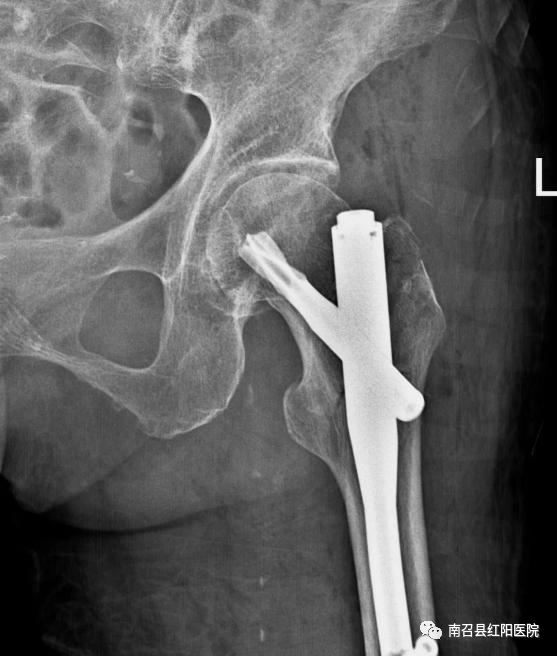

年轻人骨骼肌肉结实,除非是十分巨大的暴力作用,一般摔倒并不容易发生骨折。老年人,骨质开始变得疏松,肌肉萎缩,特别是绝经后妇女,骨质丢失更加严重。这时候髋部非常脆弱。一旦发生摔倒、滑倒,身体扭转倒地,就很容易造成髋部骨折。老年人髋部骨折后翻身和坐起疼痛不便,一般髋部骨折保守牵引治疗通常要 2~3 个月甚至更长,一旦长期卧床,就很容易造成呼吸系统感染、泌尿系统感染、深静脉血栓和褥疮等并发症,生活质量更低,进而危及生命。传统认为老年人骨折最好保守治疗,部分家属会说:“年纪大了,不再冒险受罪,不考虑手术了”,或者是担忧能否能耐受手术风险。事实上,随着医疗技术,特别是麻醉进术的快速提高,老年髋部骨折绝对禁忌症非常少。术前多学科联盟细致全面准备,使得许多百岁老人受益于外科治疗而快速恢复。目前对于股骨颈骨折一般采取人工关节置换术,对于粗隆间骨折多采用髓内钉内固定,部分患者也可以采用人工髋关节置换术,两种手术都很成熟。手术时间可控制在一个小时之内,出血量很少,绝大多数老人都可以耐受。术后一周内患者可以部分负重下床活动,避免卧床护理压力及卧床并发症。近日我院收治多例髋关节骨折病人,大部分为高龄、合并基础病较多,其中一老年女性,96岁,高龄,股骨转子间骨折,心肺功能较差,手术风险高,但患者家中困难,只有一个儿子在身边照顾,且儿子已经70余岁高龄,本身身体不好,家属为求后期方便照顾、减轻家庭负担遂要求手术治疗,积极术前检查,充分评估患者心肺功能,术前请麻醉科、代主任、王院长会诊,将手术及麻醉风险降至最低,充分评估病情后行股骨转子间骨折切开髓内钉内固定术,麻醉及手术顺利,患者术后恢复良好,现患者可坐立、屈膝屈髋及自己翻身,术后活动明显改善。